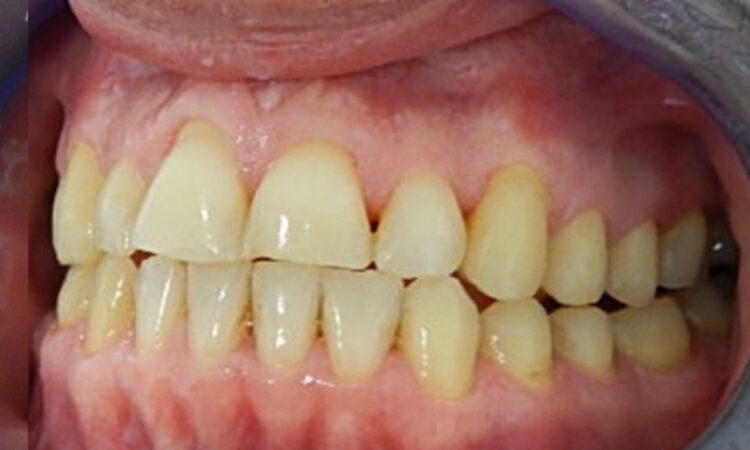

Before - puredental After - puredental

Case 19 - Invisalign®